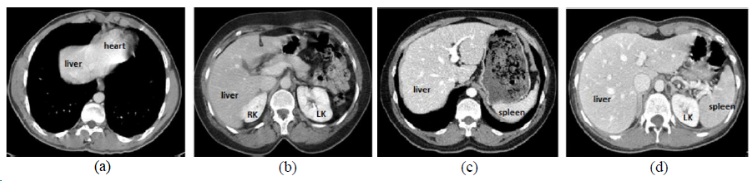

CHAOS

| 名称 | 标注内容 | 类型 | 模态 | 数量 | 标签格式 | 文件格式 |

|---|---|---|---|---|---|---|

| CHAOS | 肝/肾/脾 | 分割 | CT+MRI | 40CT+120MRI | 0/1标签 | dcm |

CHAOS是一个多脏器,多模态分割数据集。